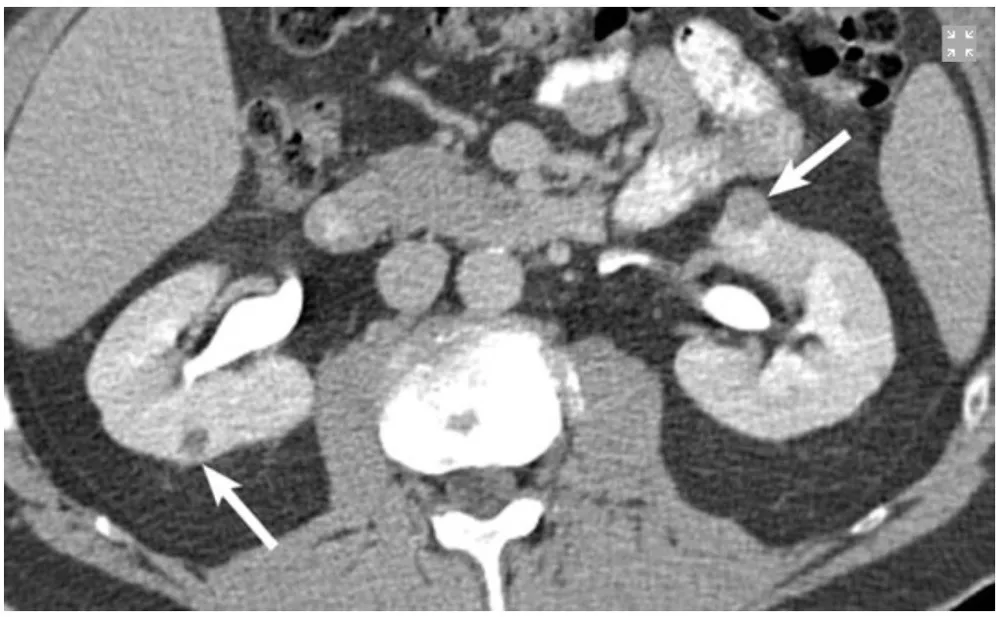

Paciente com antecedentes de carcinoma de células renais claras ressecado previamente, apresenta em exame de controle a seguintes imagens.

Na imagem 1: Um pequeno tumor exofítico com realce se projetando a partir da face anterior do polo superior do rim esquerdo (seta). Além disso, há uma lesão de 4 mm na face posterior do rim direito. Paciente foi submetido à enucleação cirúrgica da lesão renal esquerda. O tumor renal direito foi tratado com ablação por radiofrequência.

Na imagem 2 é possível identificar a sonda de radioablação.

Nos pacientes múltiplos tumores renais devemos suspeitar imediatamente de Doença de Von-Hippel Lindau, nesses casos devemos procurar tratamentos que visem poupar massa renal, uma vez que a recorrência dos tumores é a regra.